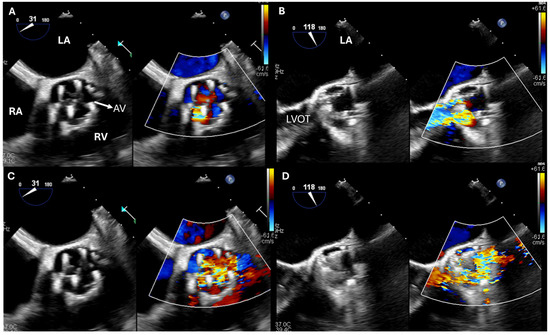

健康・医学 Perioperative Transesophageal Echocardio 51-O7MnJDyL.jpgの詳細情報

51-O7MnJDyL.jpg。Amazon | Practical Perioperative Transoesophageal。Intraoperative Transesophageal Echocardiographic Guidance in。Perioperative Transesophageal Echocardiography Self-Assessment and Review周術期経食道心エコ-図-効率的に学ぶためにの原著です。Basic Perioperative Transesophageal Echocardiography。2008年出版のため内容はかなり古いですが、翻訳版と並べて使うことで経食道心エコーまわりの英語について学習できます。。TOEIC650点の英弱ですが JBPOTで周術期経食道心エコ-図-効率的に学ぶためにを使って学習したあとこの本をつかってPTEeXAMに合格できました。運動療法のための機能解剖学的触診技術 上肢 下肢・体幹2冊セット。写真の通り書き込みがありますがシャーペンなので消せます。歯周補綴の臨床と手技 佐藤直志著。また写真の通り表紙は折れ曲がっています。新・口腔外科はじめましょう。中古品であることご理解の上での購入をお願いします。Photographic Atlas of Anatomy 第9版 解剖アトラス。